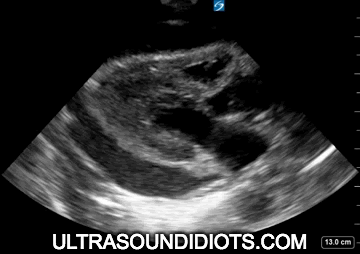

Potential False Positives (Mimickers)

Pericardial fat pad. See Figures 3a, 3b. Note the adipose tissue within the pericardium. Note hyper-echoic densities that move with the RV free wall.

Left pleural effusion. See Figures 3c, 3e, 3f, 3g. Note that Figure 3d is actually an extremely large pericardial effusion with a trace pleural effusion posteriorly.